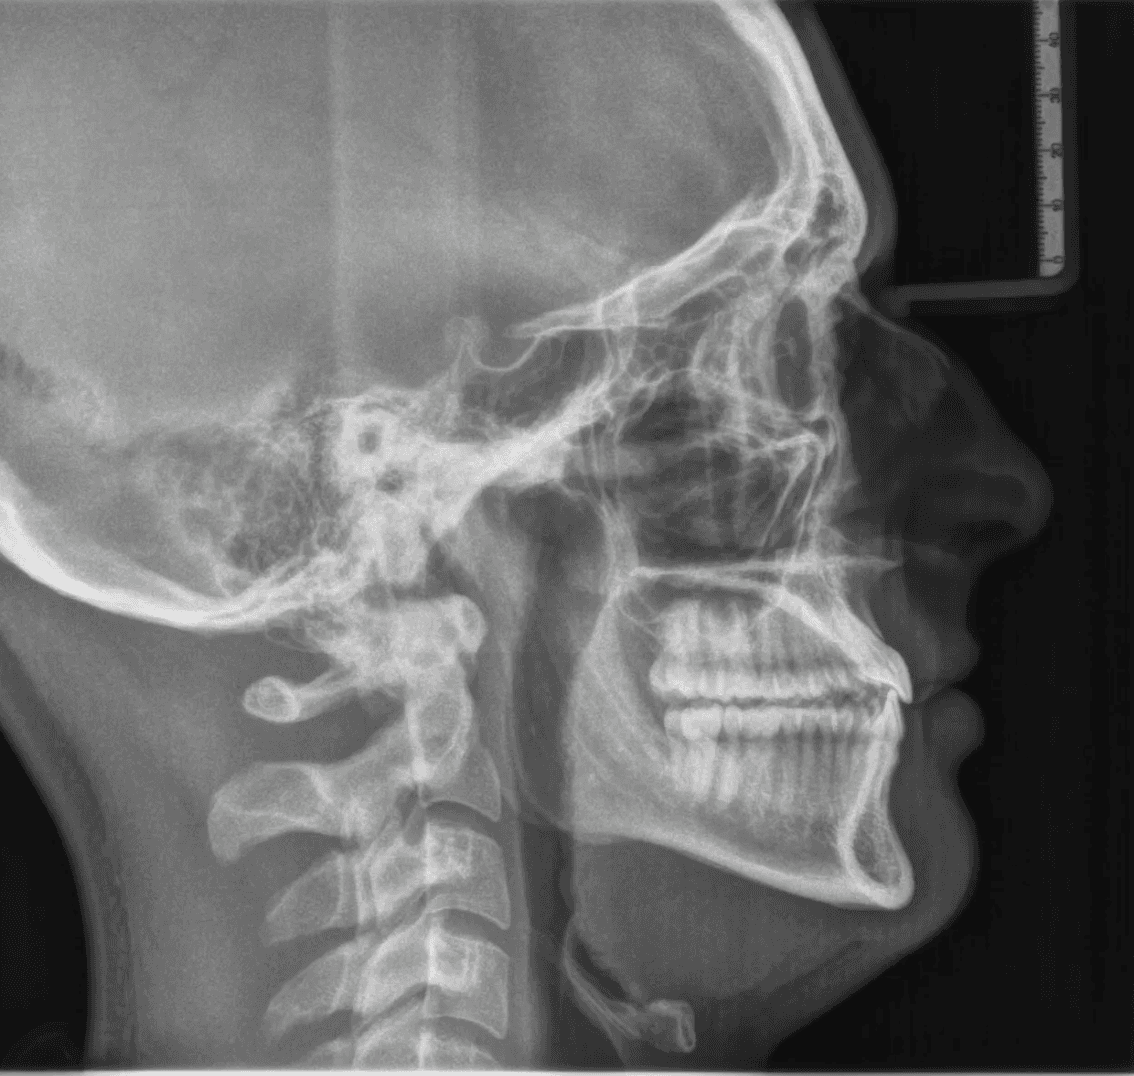

Final results

X-RAYS